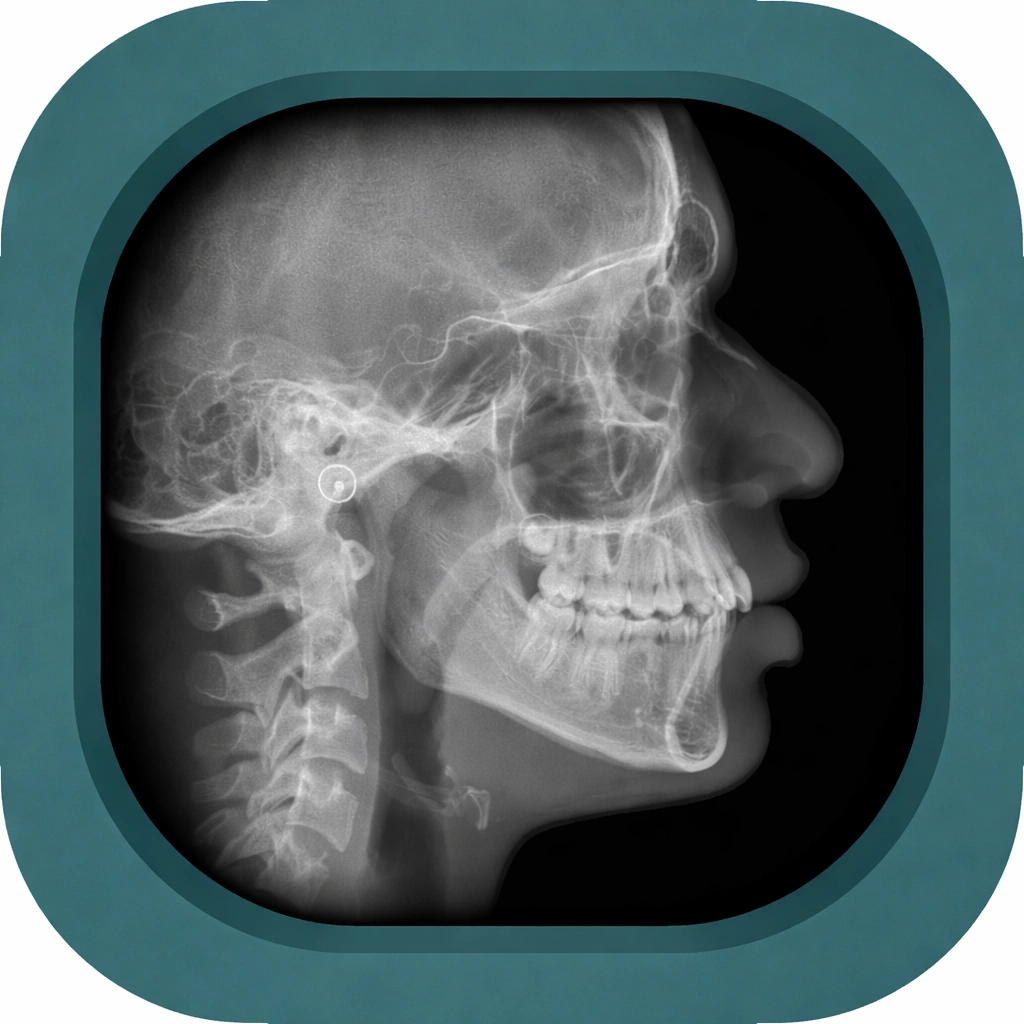

Explore high-quality X-ray anatomy from head to toe. Our database features carefully labelled images to visualize fine structures—perfect for radiologists, students, and surgeons.